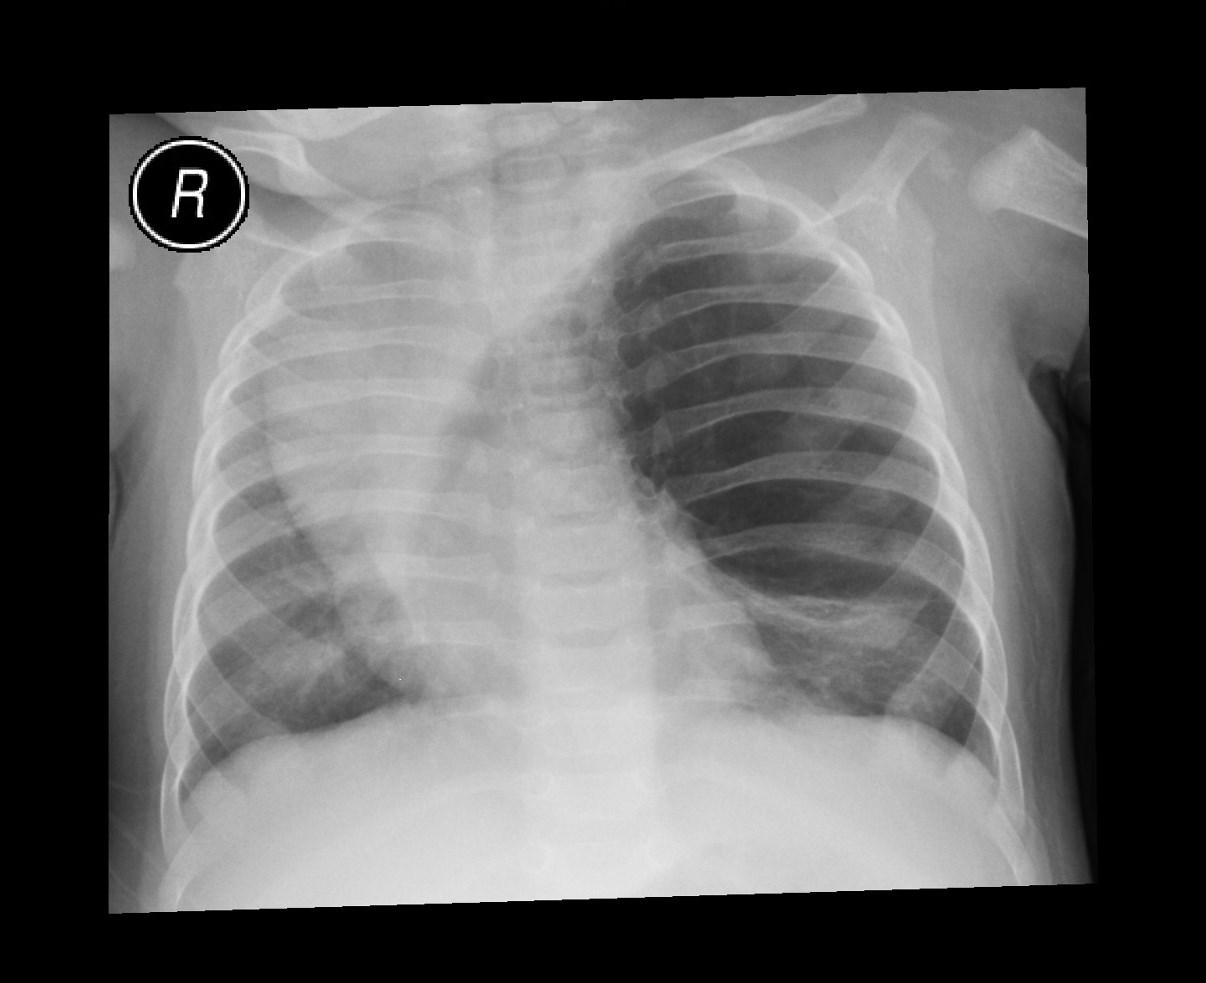

What pulmonary disease is this patient likely to develop?

Kartegners Syndrome

Triad of this condition